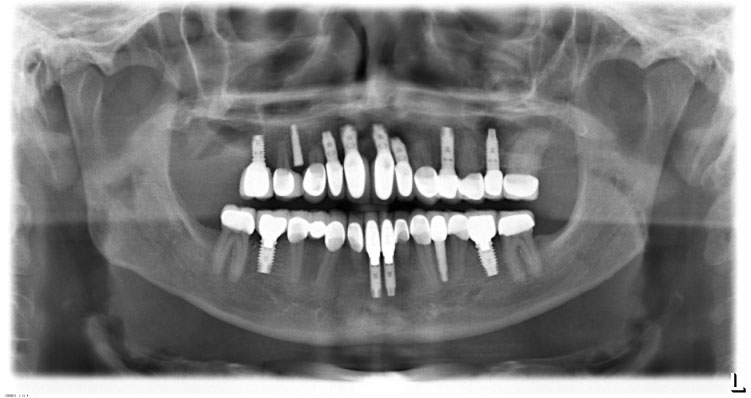

In November 2007, a male patient with ICD10 (K00.0; K07.1) asked for treatment. The diagnosis included craniomandibular malfunction, dysgnathia class III, maxillary retrognathia with horizontal and transverse narrowing of the maxilla, mandibular prognathia with lingual tipping of the mandibular front teeth (Figure 1). Additionally, we diagnosed multiple missing of permanent teeth and hypodontia of deciduous teeth with cones (Figure 2, Figure 3 and Figure 4). Systemically, the patient suffered from platelet deficiency and thrombocytopenia.

Figure 3: Orthopantomography before treatment. View Figure 3

Figure 15: Orthopantomography at the end of treatment. Implant 14 not charged. View Figure 15

We measured good osseointegration > 80 on the Ostell ISQ-scale after this comprehensive corrective osteotomy and the successful healing of the augmentation even for the enossal implants. Facial proportions and the profile expression showed harmonized. The dental situation was satisfying in function as well as in the esthetic aspect (Figures 3). The dentolabial analysis showed good visibility of the teeth in neutral position with cutting edges of 2 mm. Interinzisal lines and middle facial lines assorted well, occlusion and commissure line corresponded. The mandibular-maxillary relation was fixed as central occlusion with maximum intercuspidation Figure 3.